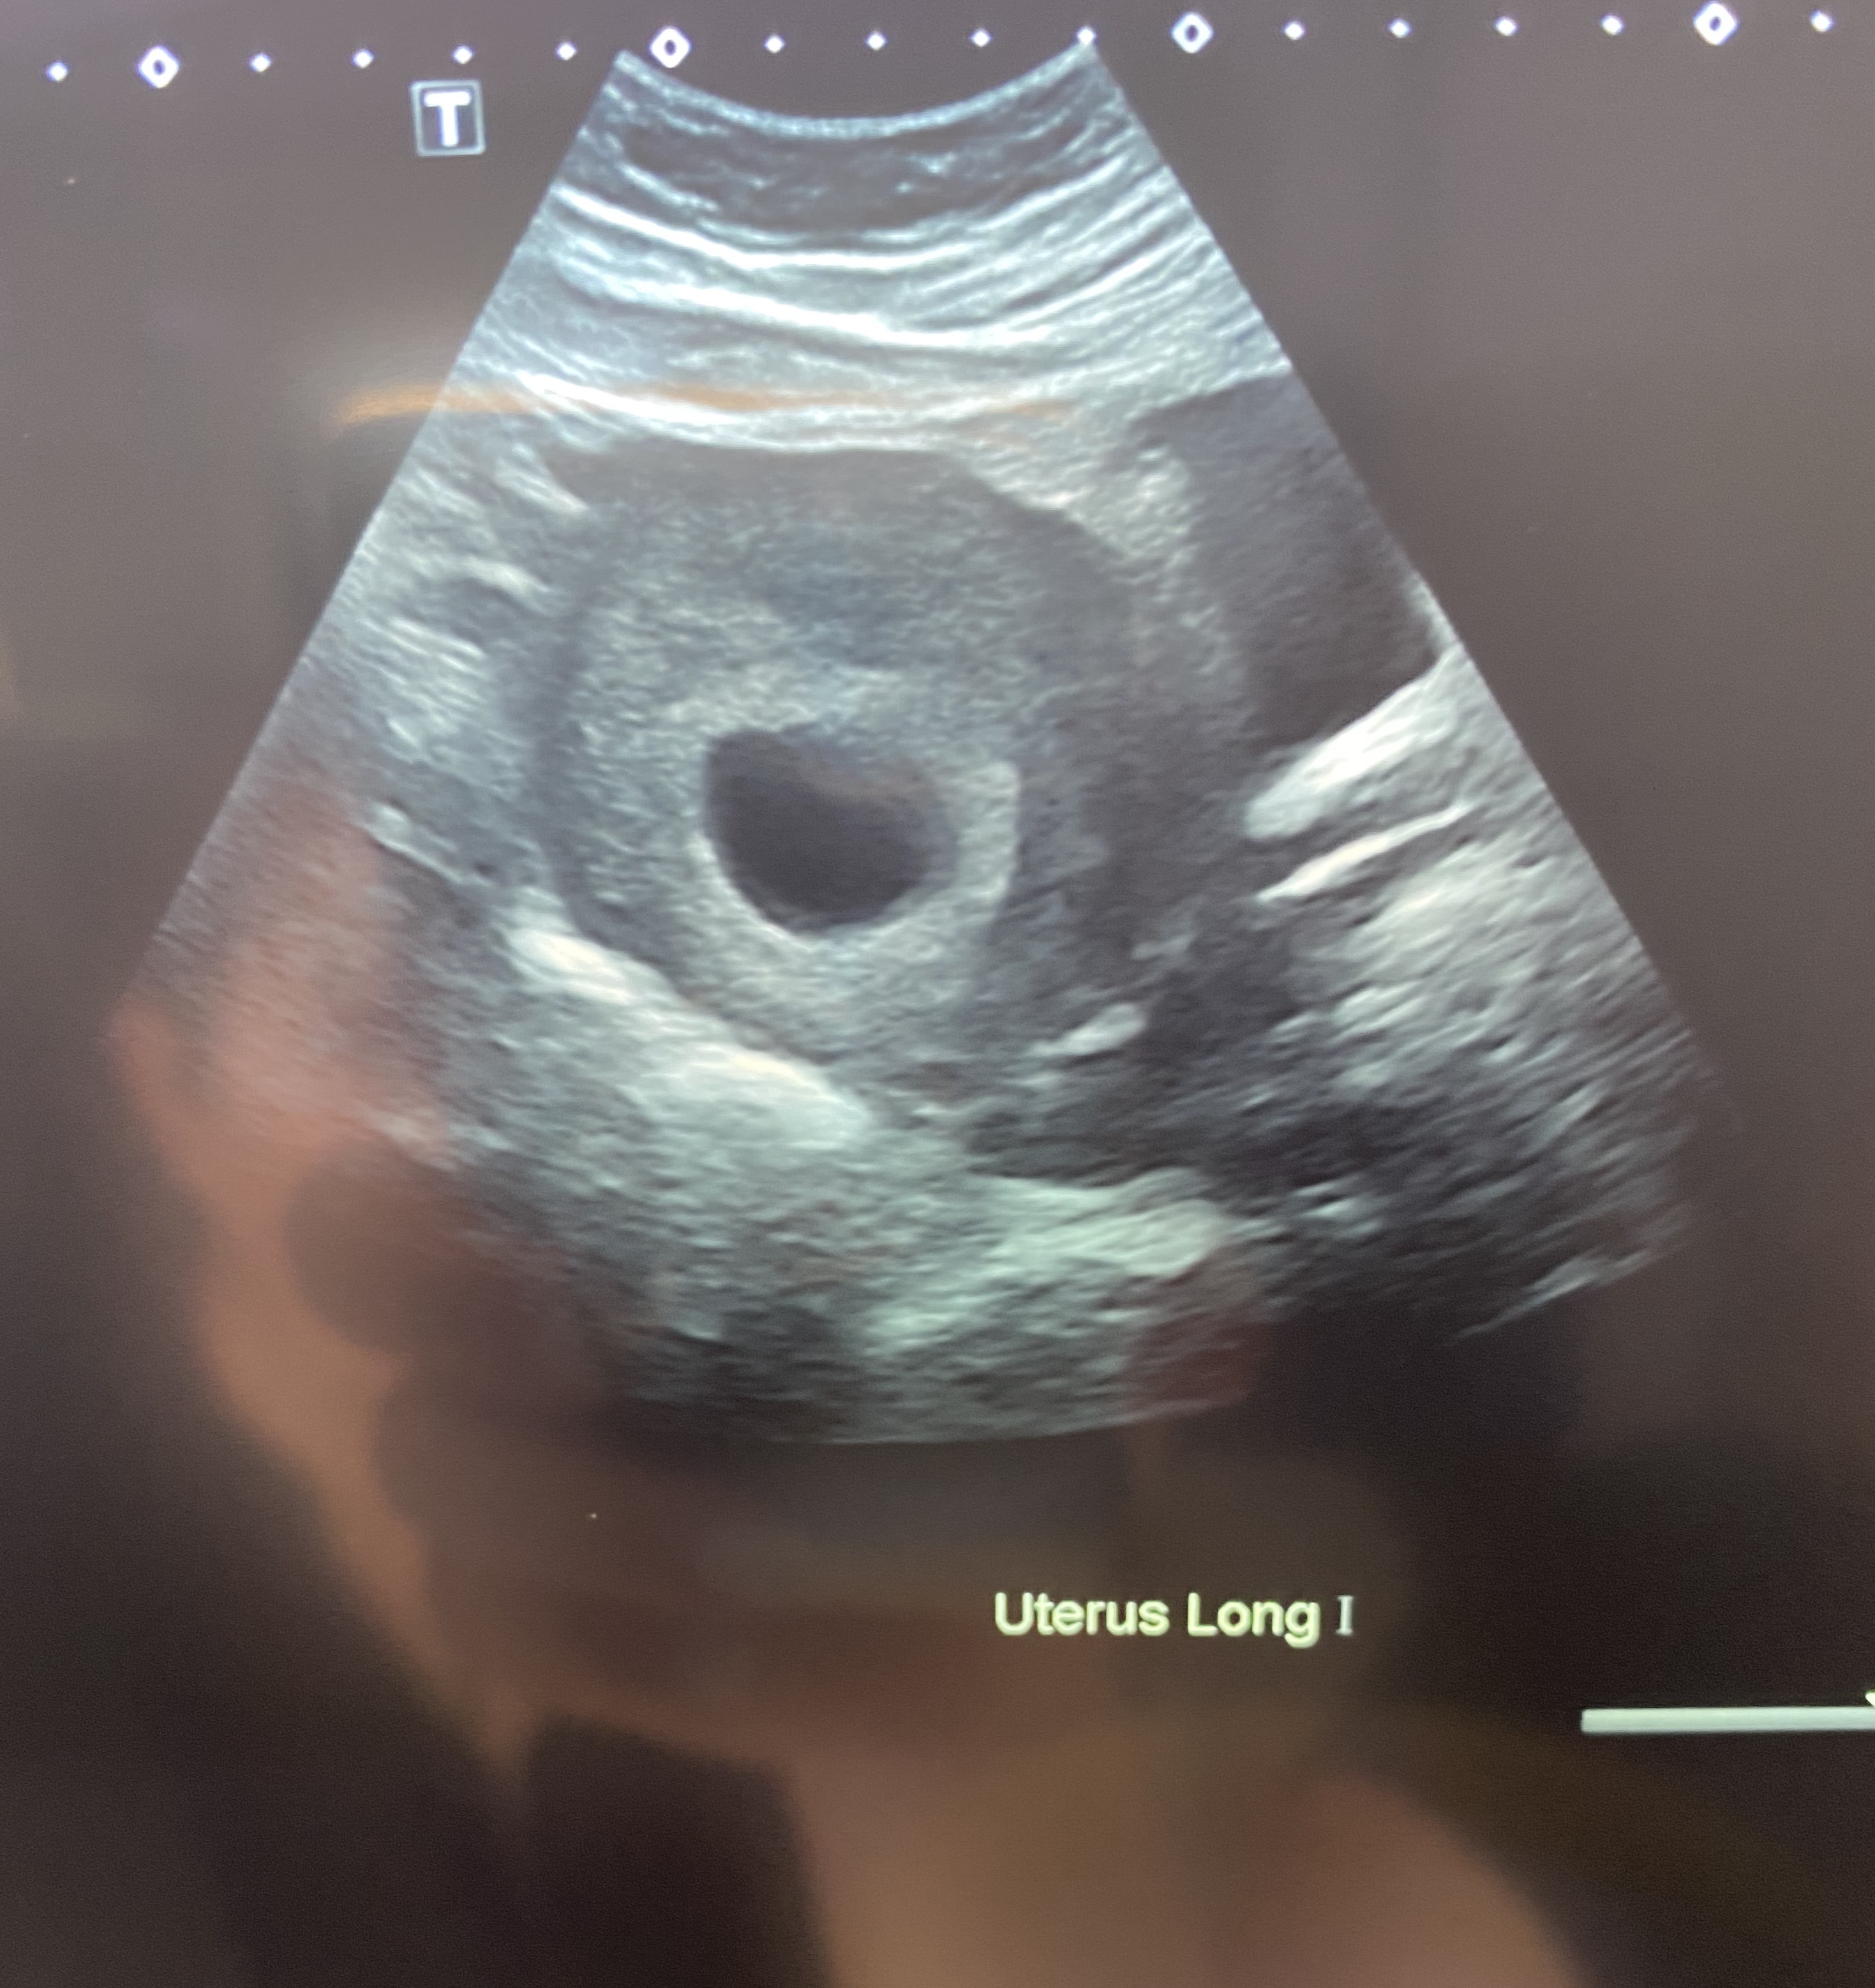

I’m currently 7w4d.

Anyway here are a couple images from the scan, it was an abdominal one. Anyone have any Ramzi guesses? We’re going to stay team green but I like to hear guesses, just for fun :)